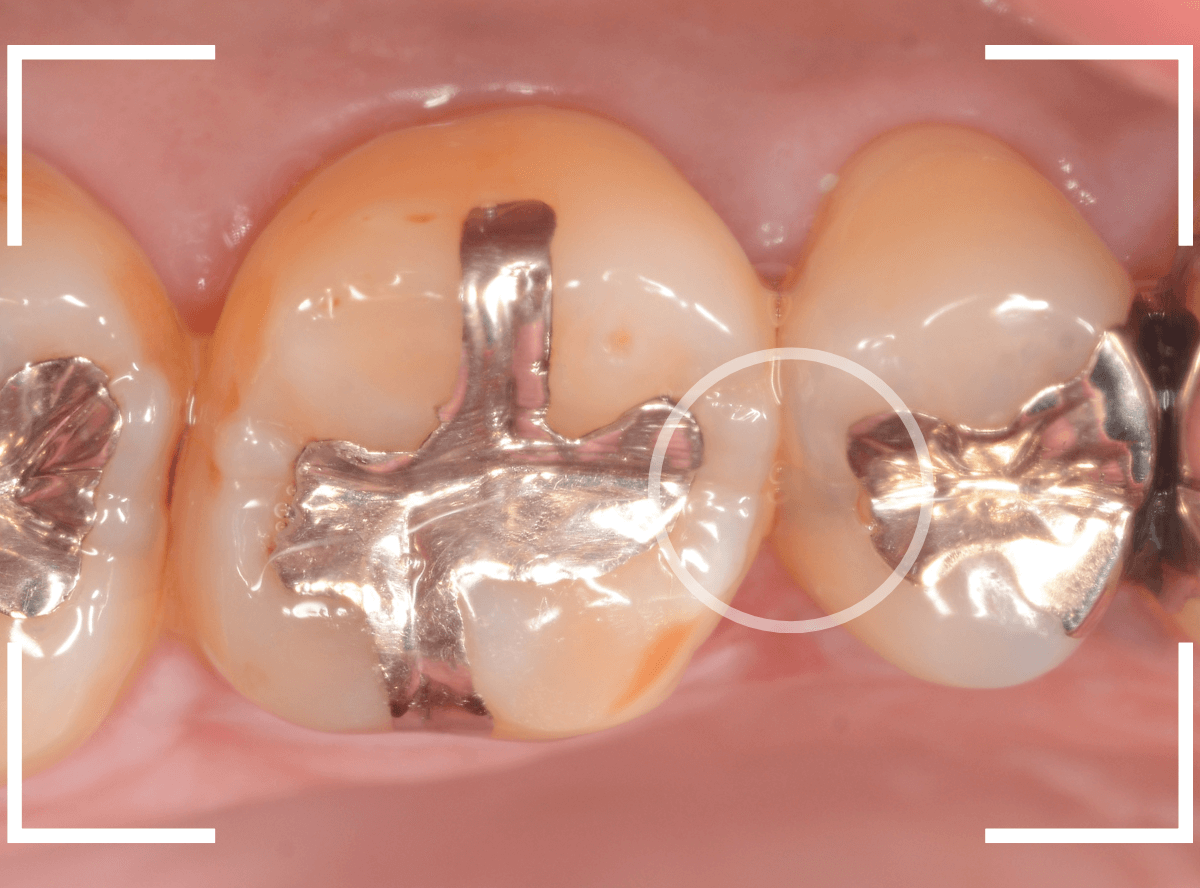

Case.25 レントゲン所見と目視を頼りに、虫歯治療

検査時に〇部、歯と歯の間の小臼歯部に虫歯らしき黒い影があるのが見つかりました。

かなり怪しいですが、メタル・インレーが入ってるので、それが透けている可能性もあります。

レントゲン写真で確認します。

レントゲンでは後ろの大臼歯部の方が虫歯になっているように見え、小臼歯部は問題ないように見えます。

まず大臼歯のインレーを外して、中を調べます。